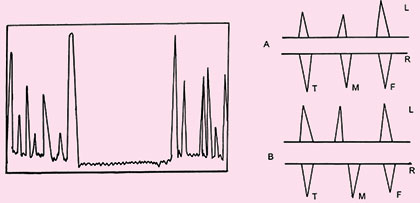

As the frequency of ultrasound used in diagnostic application is about 1 MHz or 1000000 cycle/sec. The duration of emitted sound pulse is one micro second (1 μ sec), and these pulses are repeated about 1000 times per second (PRF=1KHz) (Fig. 1.2).

Fig. 1.2: The pulse-echo timing of data acquisition depicts the initial pulse occurring in a very short span (the pulse duration) and the remained of the time listening for echoes before the next pulse (the pulse repetition period)

- A mode: A mode (amplitude mode) is the most basic form of diagnostic ultrasound, here a single beam of ultrasound is analyzed, hence in this mode the ehoes are shown as peaks and the distance between the various structures and transducer can be measured (Fig. 1.12) and is displayed on time axis. Time and distance are interchangeable because an echo is assumed to travel at a constant speed in the body tissue (1540 m/sec), time it takes for the echo to return to the transducer can be converted to the distance. This mode is now almost obsolete (Fig. 1.12).

- M mode: If the series of B mode are displayed on a moving time base, the motion of mobile structure can be observed. This process forms the basis of echocardiography (Fig. 1.14).

Fig. 1.14: M-mode of display changes of echo amplitude and position with time. Display of changes in echo position is useful evaluation of rapidly moving structures such as cardiac valves and chamber walls. Here the three major moving structures in an M-mode image of fetal heart corresponds to the near ventricular wall (A) interventricular septum, (B) the far ventricular wall (C) the base line is a time scale and permits calculation of heart rate and M-mode data